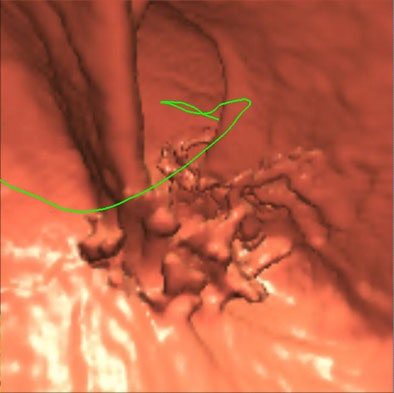

| Three-dimensional endoluminal view (above) and 2D MPR (below) of a patient who underwent prepless VC with the aid of a NutraPrep (E-Z-EM) low-residue diet for two days before imaging, and 120 cc of MD-GastroView (Mallinckrodt, Hazelwood, MO) iodinated oral contrast the night before the exam. |

"The problem with doing a 3D fly-through is that you may see an area where there are an awful lot of these pseudopolyps (false positives)," Choi said. "In some portions where the colon is relatively clean, you can actually make out the wall, but in most cases the current generation of VC software does not allow for the efficient subtraction of contrast-tagged solid stool."

The digital subtraction software leaves subtraction artifacts; partial volume artifacts, motion artifacts, foreign bodies, and extrinsic masses must also be dealt with. "Differentiating between true polyps and pseudopolyps is hard," Choi said. "My conclusion is that you cannot read laxative-free VC with 3D."

Instead of 3D, Choi said his group uses a magnified 2D multiplanar reconstructed (MPR) view of the colon wall that is orthogonal to the centerline of the colon, read, like 3D, on the Viatronix workstation.